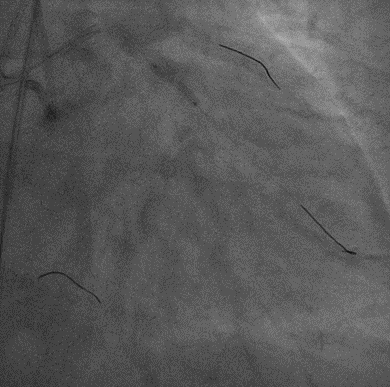

手术影像

左冠优势,LM、LCX未见狭窄,TIMI3级;LAD近段CTO,TIMI0级

RCA细小,近中段狭窄40%-50%,TIMI3级;远端可见LAD侧枝血流

策略讨论:近端纤维帽不清晰,LAD中段显影可见,闭塞段长度>20mm。间隔支逆供条件尚可。CTA提示LAD多发钙化。尝试正向开通,优选亲水性滑导丝,若失败,及时调整逆向策略。